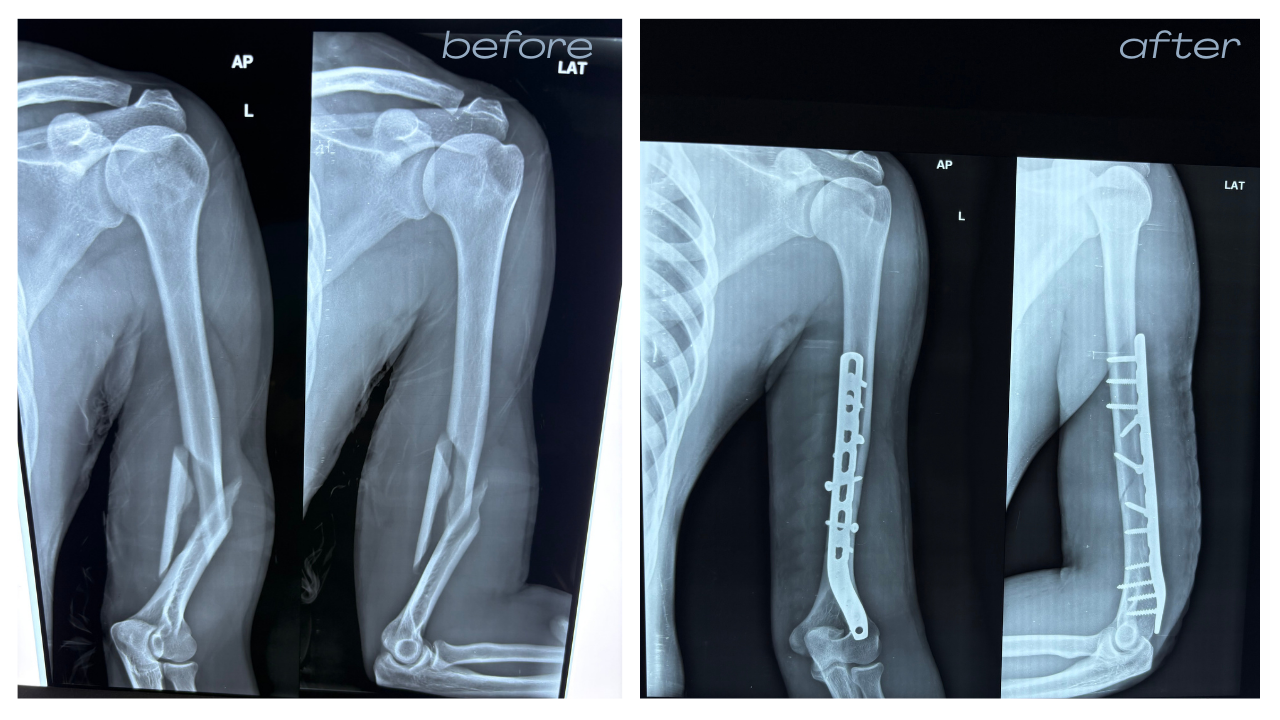

Accident & Trauma Care – Specialized in Bone & Joint Injuries.

- Trauma & Fracture:

Emergency Bone Care.

Over 8,000 successful orthopedic procedures, ranging from complex trauma to total joint replacements.